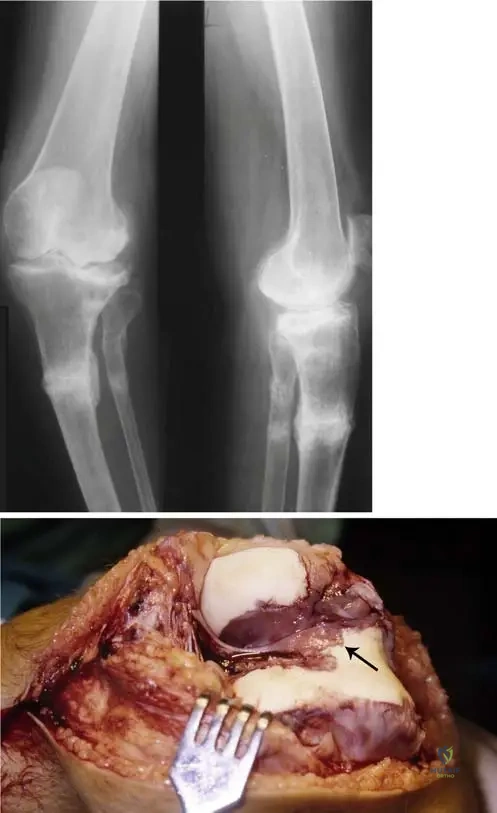

Question 70

A 55-year-old female with long-standing rheumatoid arthritis undergoes a knee arthroscopy for persistent pain and swelling. Intraoperative findings reveal an extremely hypertrophic synovium filling the intercondylar space, with visible invasion of the cartilage surface by this tissue.

View Answer & Explanation

Correct Answer: C

Rationale: The hypertrophic synovial tissue, known as pannus, is characteristic of rheumatoid arthritis. This proliferative pannus destroys cartilage both mechanically through its expansion and by releasing enzymes that degrade the cartilage matrix. This is a central pathomechanism of joint destruction in RA. The main distractor, A, is incorrect because osteophyte formation is more characteristic of osteoarthritis, not the primary mechanism of cartilage destruction in RA.